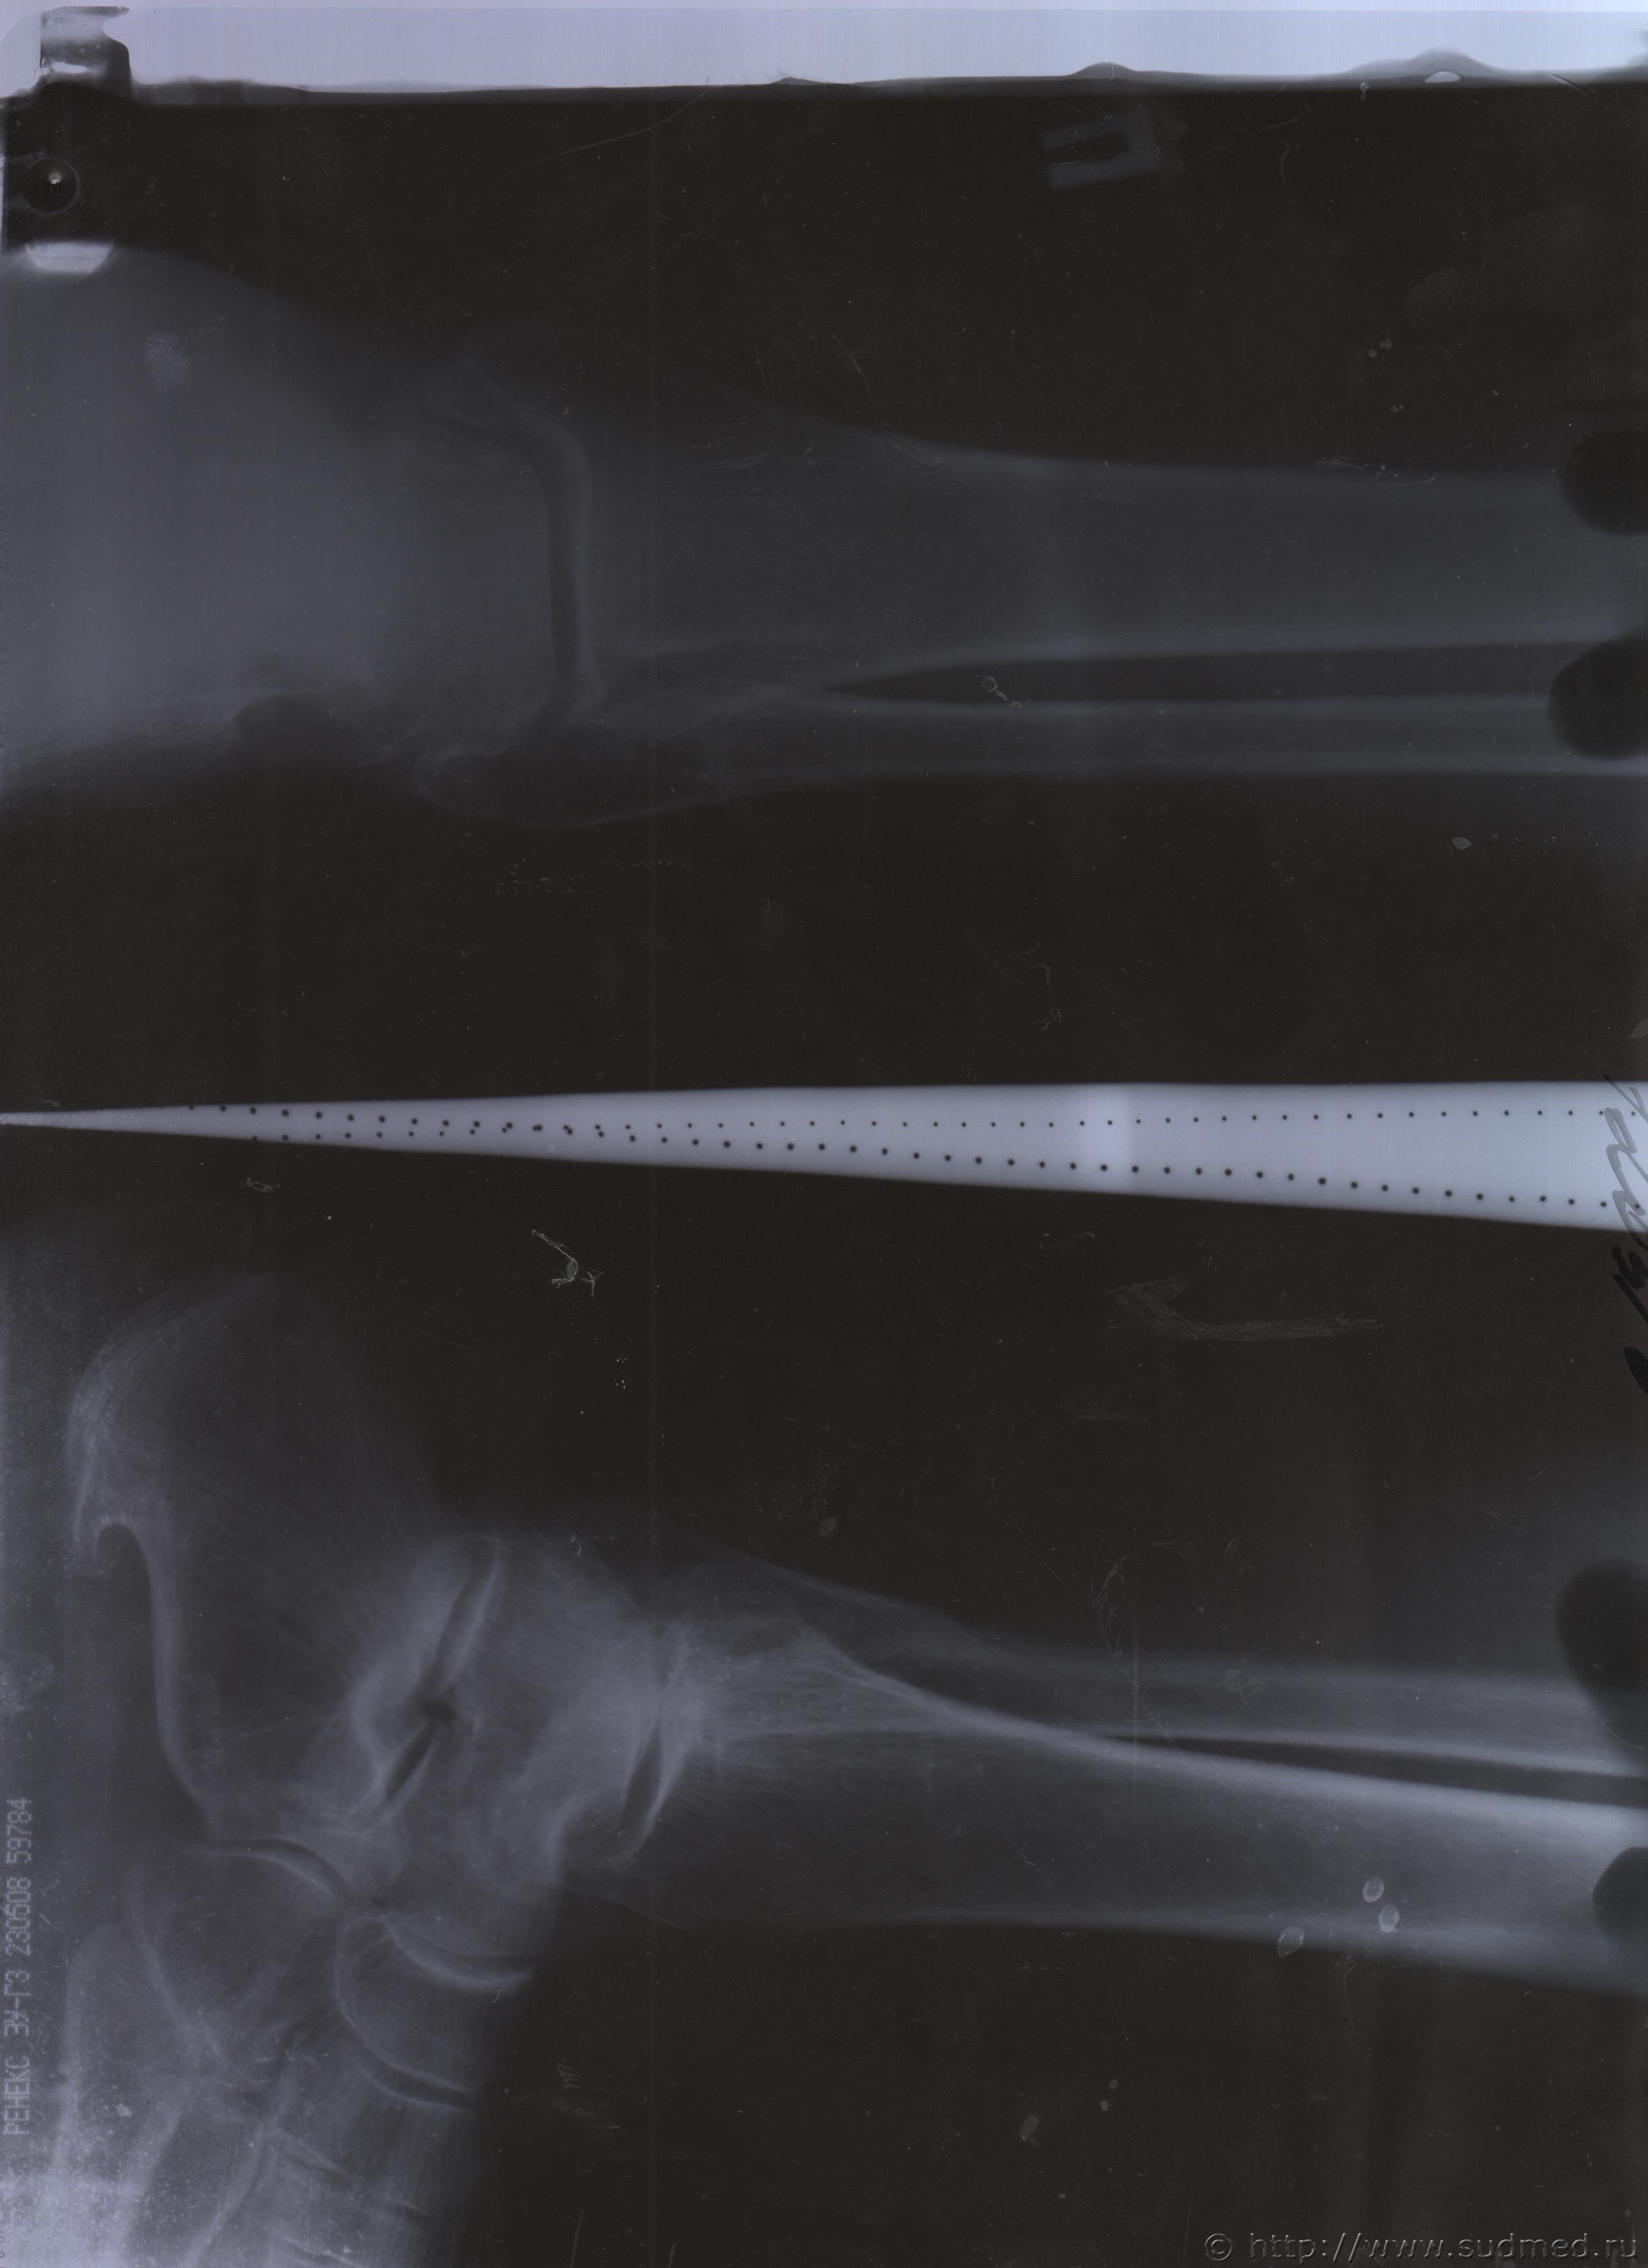

06.07.2015 г. при обращении в горбольницу мне выдали не описанный снимок( все рентгенологи были в отпуске) и справку № 4379 от 06.07.15 г. где диагноз: закрытый 2-х лодыжечный перелом правой голени без смещения. Копию справки прилагаю

За все 12 месяцев, что была на больничном, 8 раз делали снимки травмированной ноги и все заключения именно : «закрытый 2-х лодыжечный перелом правой голени без смещения».

После того, как был поставлен диагноз : «компрессионный перелом L2 позвонка поясничного отдела позвоночника». Амбулаторная мед карта, была украдена из кабинета врача травматолога. При восстановлении мед карты( в марте 2016 г.), врачом травматологом была взята копия справки от 06.07.15 г.из приемного отделения горбольницы. Справка № 4379 ( дубликат), диагноз : «закрытый 2-х лодыжечный перелом правой голени без смещения».

Уважаемые доктора, нужны ли снимки по перелому правой голени? и Заключения по МРТ и КТ.Ранее представляла результаты обследования...Сделала копию снимков по КТ и МРТ( только вот какого качества получились не знаю.)

Посмотрите, пожалуйста

Посмотрите, это снимки за 12 месяцев.

Уважаемая Татьяна! По представленным Вами снимкам ничего сказать нельзя: нет маркировки даты каждого снимка (поэтому, невозможно их сравнивать друг с другом и соотносить с датой травмы), исследование непосредственно пленок гораздо более информативно, чем анализ представленных изображений (детали костной структуры в зоне перелома практически не видны).

Рекомендую проконсультировать все эти снимки у высококвалифицированного рентгенолога. Далее - по ситуации, т.е. в зависимости от его мнения. В любом случае, есть формальные основания для назначения дополнительной экспертизы, т.к., судя по представленному Вами фрагменту заключения эксперта, на экспертизу не были предоставлены все мед.документы с данными о лечении предъявляемой травмы (Вы пишете, что рентгенограммы делались на протяжении 12 месяцев, полагаю, что Вы и врачами наблюдались в течение этого срока, т.е. велась мед.карта).